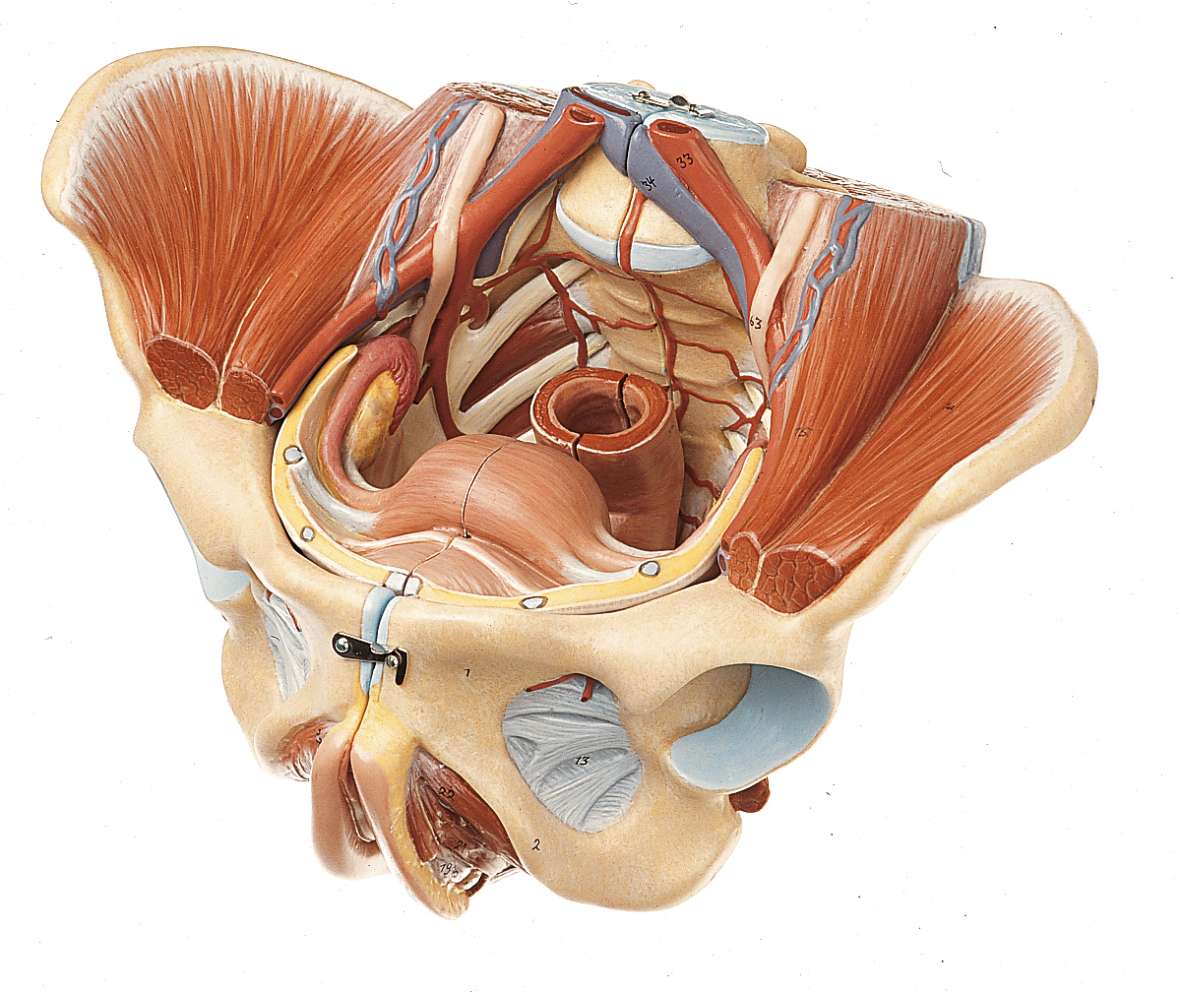

Анатомия малого таза: детальные схемы и изображения

Раздел: Образы вокруг